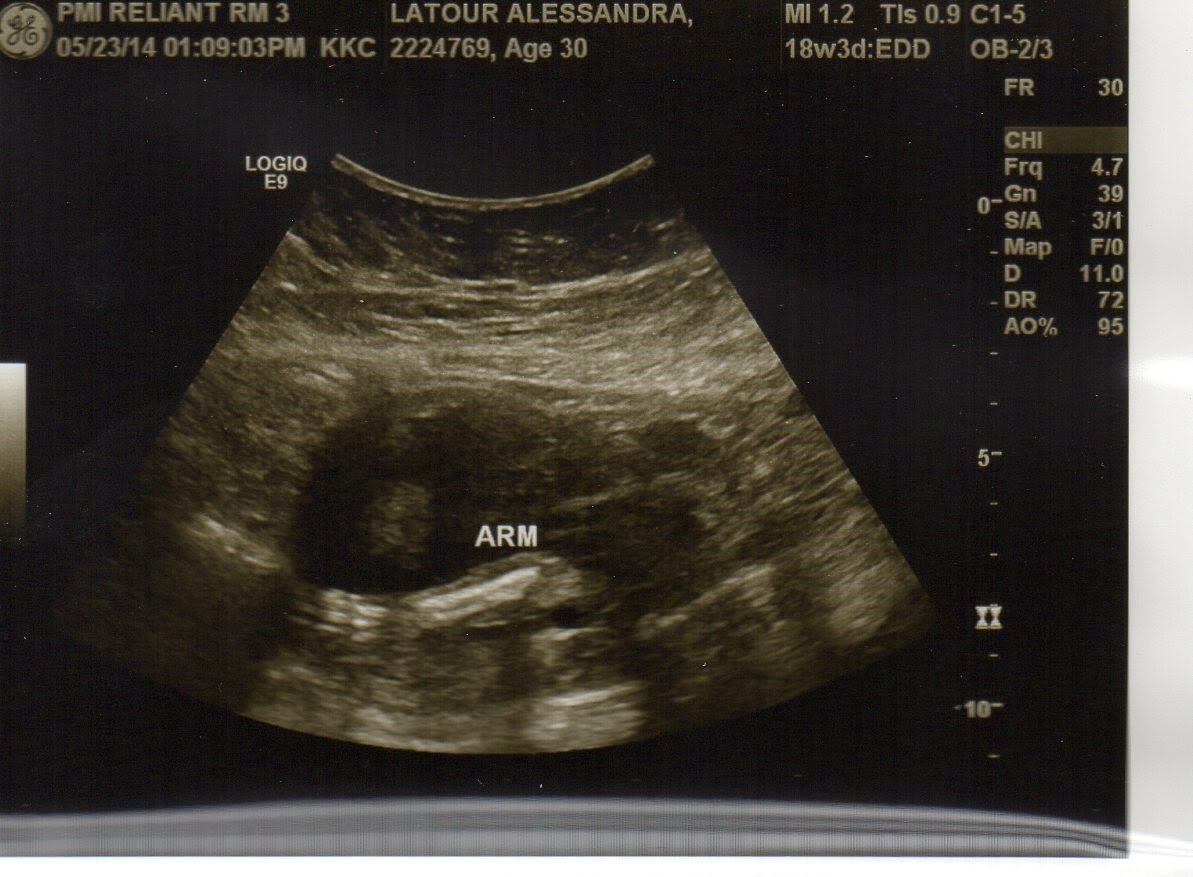

Friday we go for our next ultrasound, the one where they do the anatomy checking. Nope, we're still not going to find out if it's a boy or girl. Sorry, everyone who wants to know - you'll just have to wait till s/he makes his/her debut in October! I hope everything will look good. I am curious whether it's one of those 3D ultrasounds. They are kind of creepy! I'm not sure I want to see exactly what baby's face will look like when s/he comes out. What if s/he's ugly? Just kidding, whatever s/he looks like will be fine; we just want him/her to be healthy!

After the ultrasound is our next doctor's appointment. I will admit that I'm excited for both appointments, since it's been a month from our last one, and I'm not sure if I'm pregnant or just getting fat! It will be nice to have a new picture and hear the heartbeat and get the ok from the doctor that all is well. (It would be different if I could feel the baby kicking or see a significant baby bump, then I might be reassured without those things.)